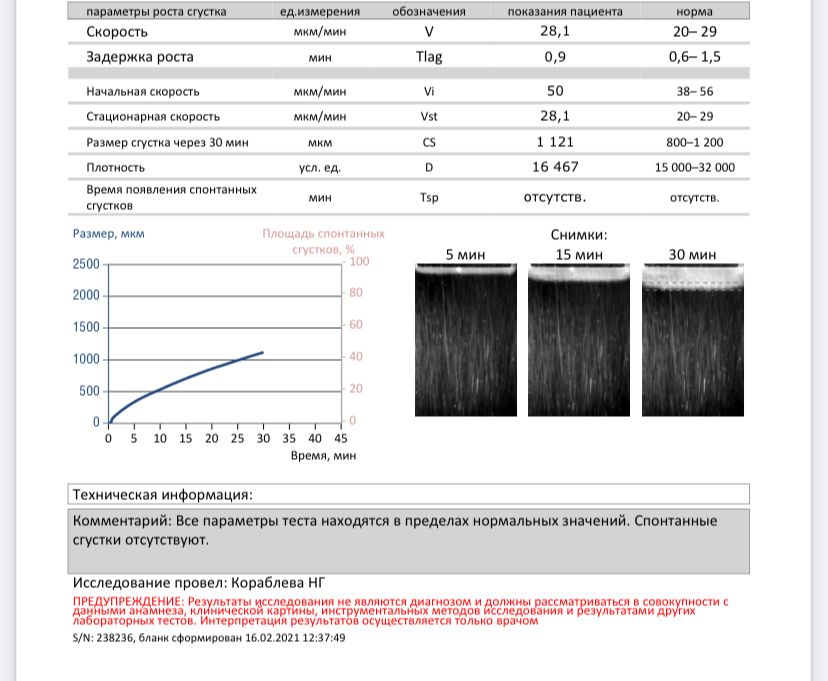

Гемостаз

Замершая беременностьДевочки, кто что понимает, подскажите пожалуйста все ли хорошо в результатах)

Жду результаты АФС чтобы пойти к врачу...